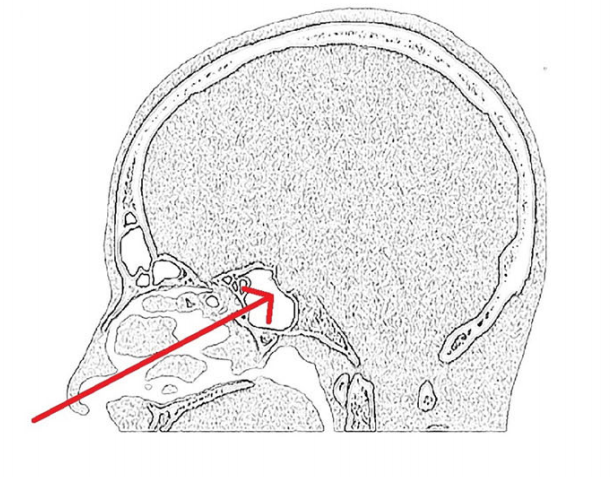

术前MRI显示上斜坡脊索瘤包裹基底动脉和左大脑后动脉。

手术入路示意图显示具体操作路径。